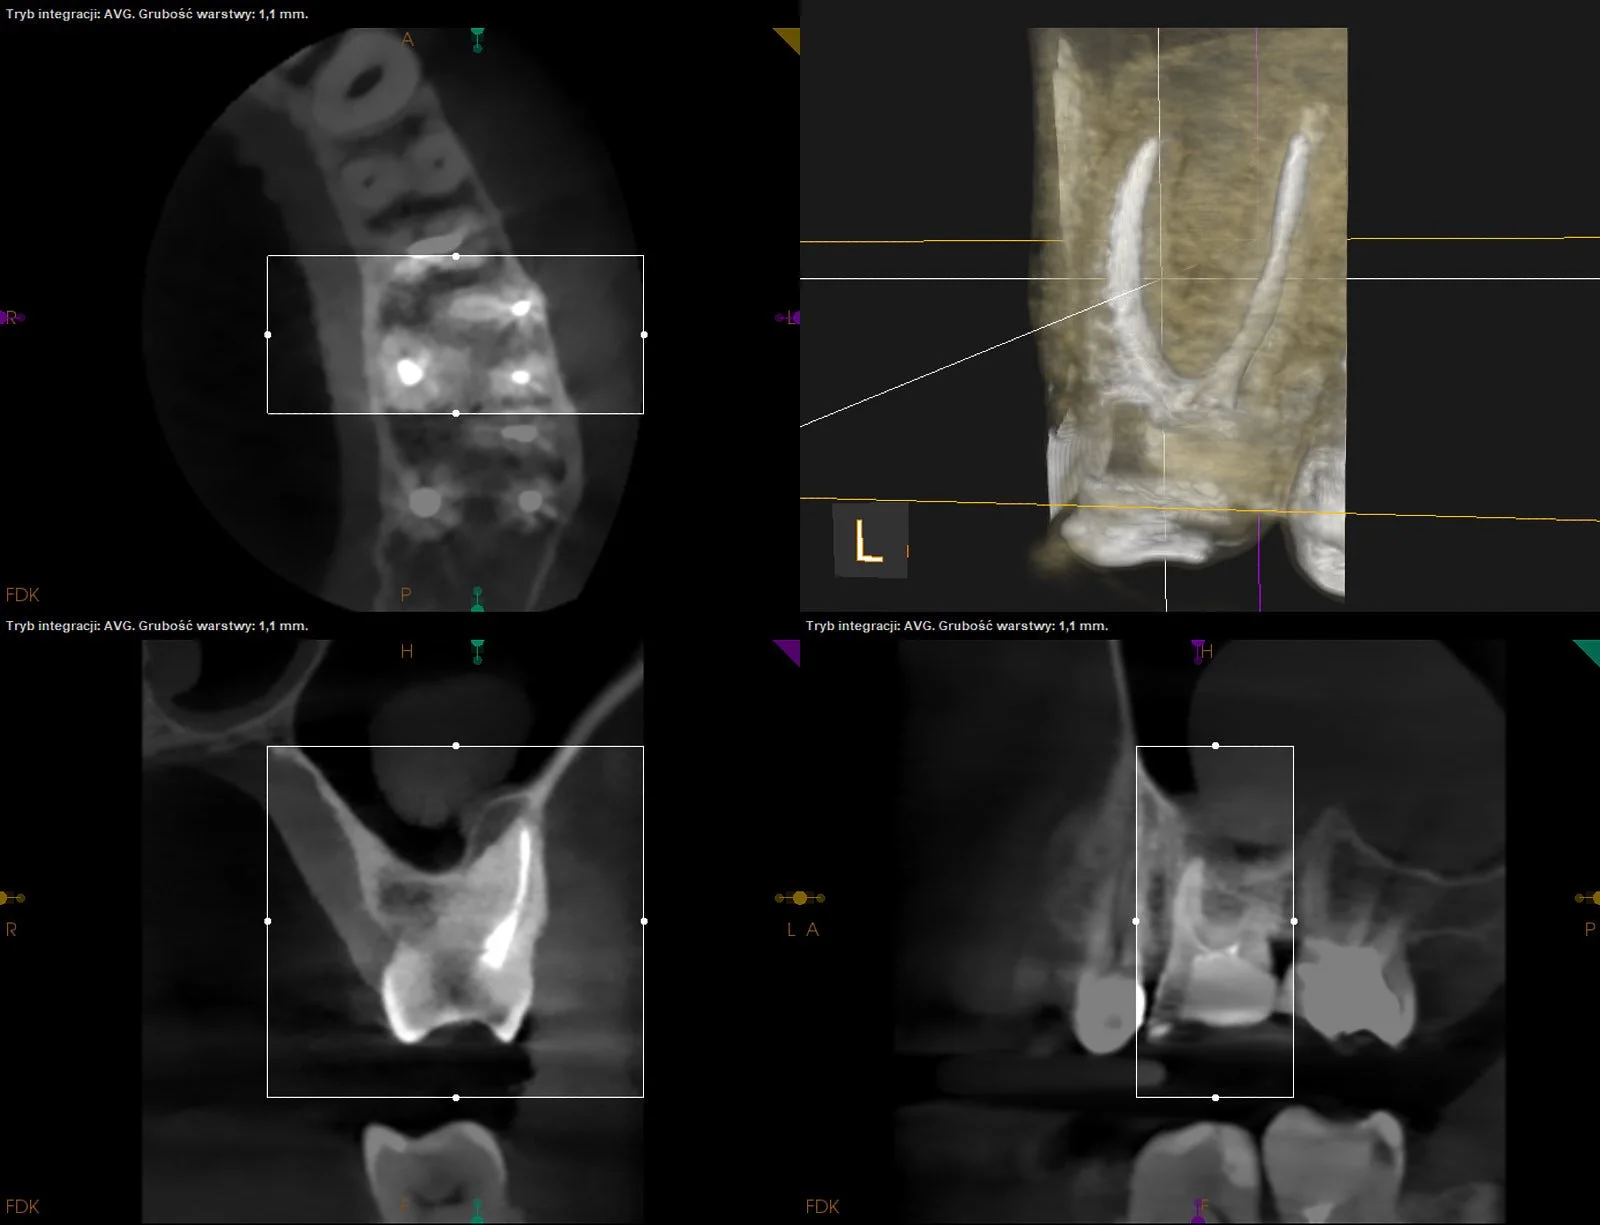

Reendo d.26. Wykonano ponowne leczenie kanałowe systemu korzeniowego z odnalezieniem i udrożnieniem pominiętego przy pierwotnym leczeniu kanału MB2 (anatomicznie typ VI w klasyfikacji Vertucciego).